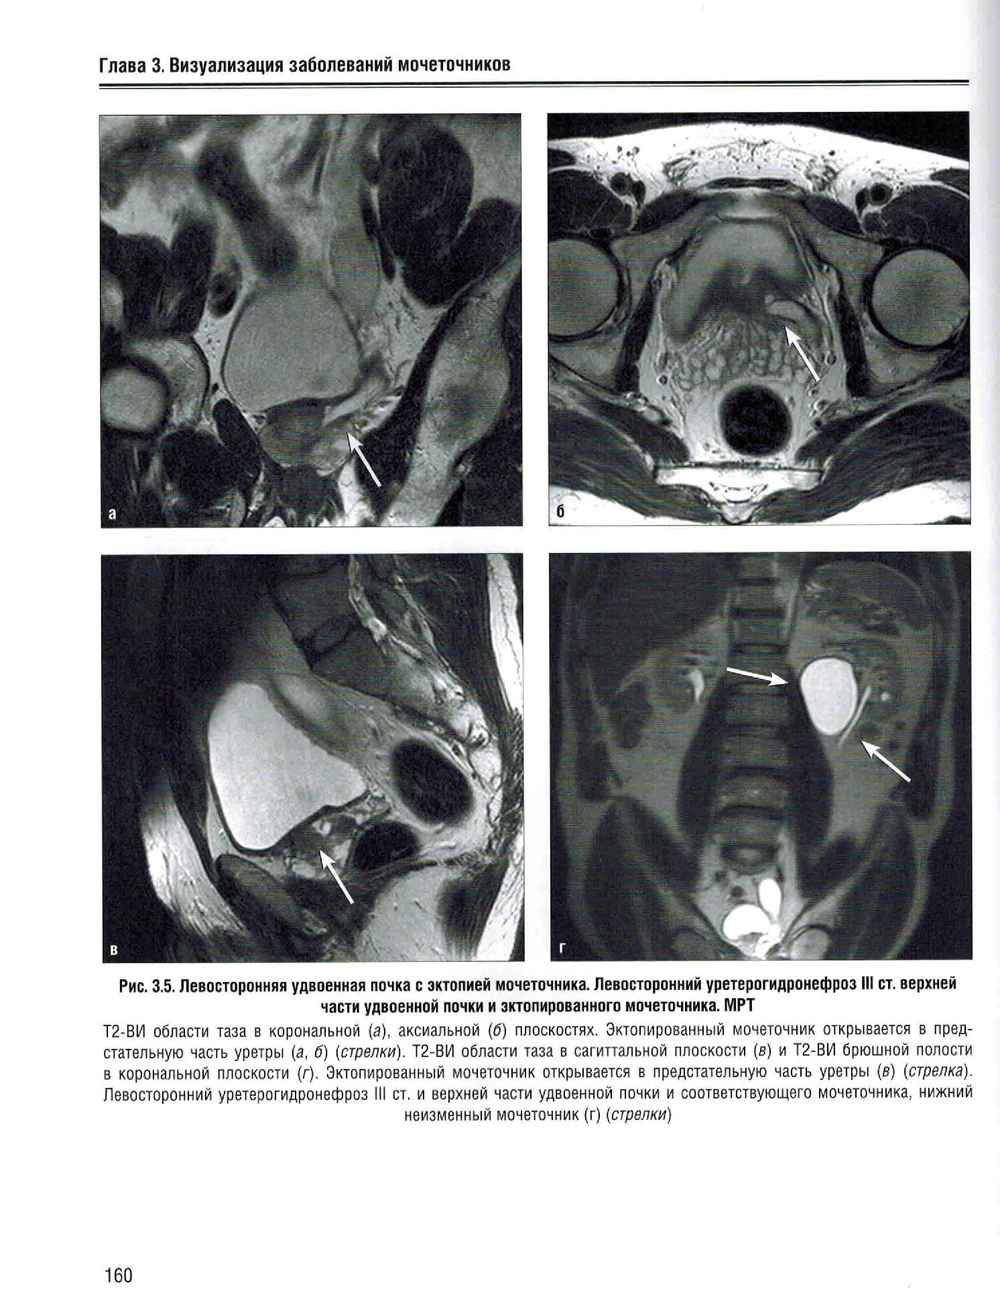

В учебном пособии изложена нормальная лучевая анатомия почек, мочеточников и мочевого пузыря по данным рентгенологического исследования, КТ, МРТ и УЗИ. Приведено описание лучевой семиотики наиболее часто встречающихся заболеваний и повреждений почек, мочеточников и мочевого пузыря с представлением данных УЗИ, КТ и МРТ. Даются рекомендации по тактике лучевого исследования, приводится дифференциальная диагностика. Рассматриваются вопросы этиологии, патогенеза, морфологии и клинические проявления заболеваний. Предназначено для ординаторов, обучающихся по специальностям: 31.08.08 - «Радиология»; 31.08.09 - «Рентгенология»; 31.08.11 - «Ультразвуковая диагностика», а также врачей смежных специальностей. Учебное пособие может быть рекомендовано для подготовки в системе непрерывного медицинского образования.| Издательство | Элби |